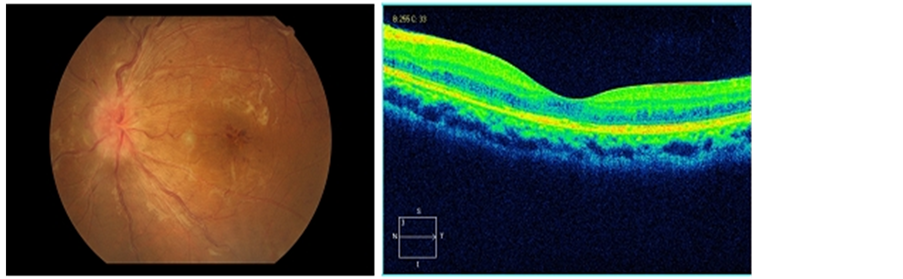

At 1 week following the IVR+SS injection, BCVA improved from 78 letters (ETDRS) at baseline to 90 letters at 1-week follow-up and maintained stable through 1-month follow-up. The CRT measured by OCT decreased from 465 μm at baseline to 240 μm at 1-week follow-up and to 226 μm at 1-month follow-up. Mean deviation (MD) measured by perimetry increased from −5.17 dB to −4.59 dB and to −4.29 dB, respectively (Table 1). Retinal hemorrhage was reduced significantly demonstrated by the fundus examination and the macular edema had completely resolved as demonstrated by OCT through the 1-month follow-up (Figures 1-3). The arm-retina circulation time (ART) was also greatly shortened when compared to the baseline. ERG results showed an overall improvement of the retinal function as compared to the baseline (Table 2). IOP was measured unchanged at 15 mmHg under given local therapy. No ocular or systemic side effects were detected.

Figure 1. The fundus examination and OCT result at baseline.

Best-corrected visual acuity (BCVA) was 100 letters (ETDRS) OD and 78 letters OS at baseline. Anterior segment examination showed normal findings. Intraocular pressure (IOP) was 15 mmHg bilaterally. Fundus examination showed diffuse optic disc edema with flame-shaped hemorrhages, macular exudation and hemorrhage as well as the twisting and dilation of the retinal veins in LE. Fundus examination showed normal findings in RE. Fluorescein angiography (FFA) demonstrated optic disc swelling, intraretinal hemorrhage and macular edema in LE. The arm-retina time (ART) was also obviously prolonged. The findings in RE were normal. Automated perimetry showed, in LE, a minimum defect linked with physiologic scotoma. Central retinal thickness (CRT) was measured by optical coherence tomography (OCT) as 465 μm. Electroretinogram (ERG) was also done to have an overall idea of the retinal function.